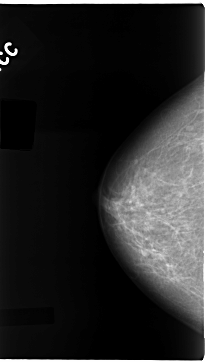

C_0108_1.RIGHT_CC

RIGHT_CC LINES 4696 PIXELS_PER_LINE 2656 BITS_PER_PIXEL 12 RESOLUTION 50 NON_OVERLAY